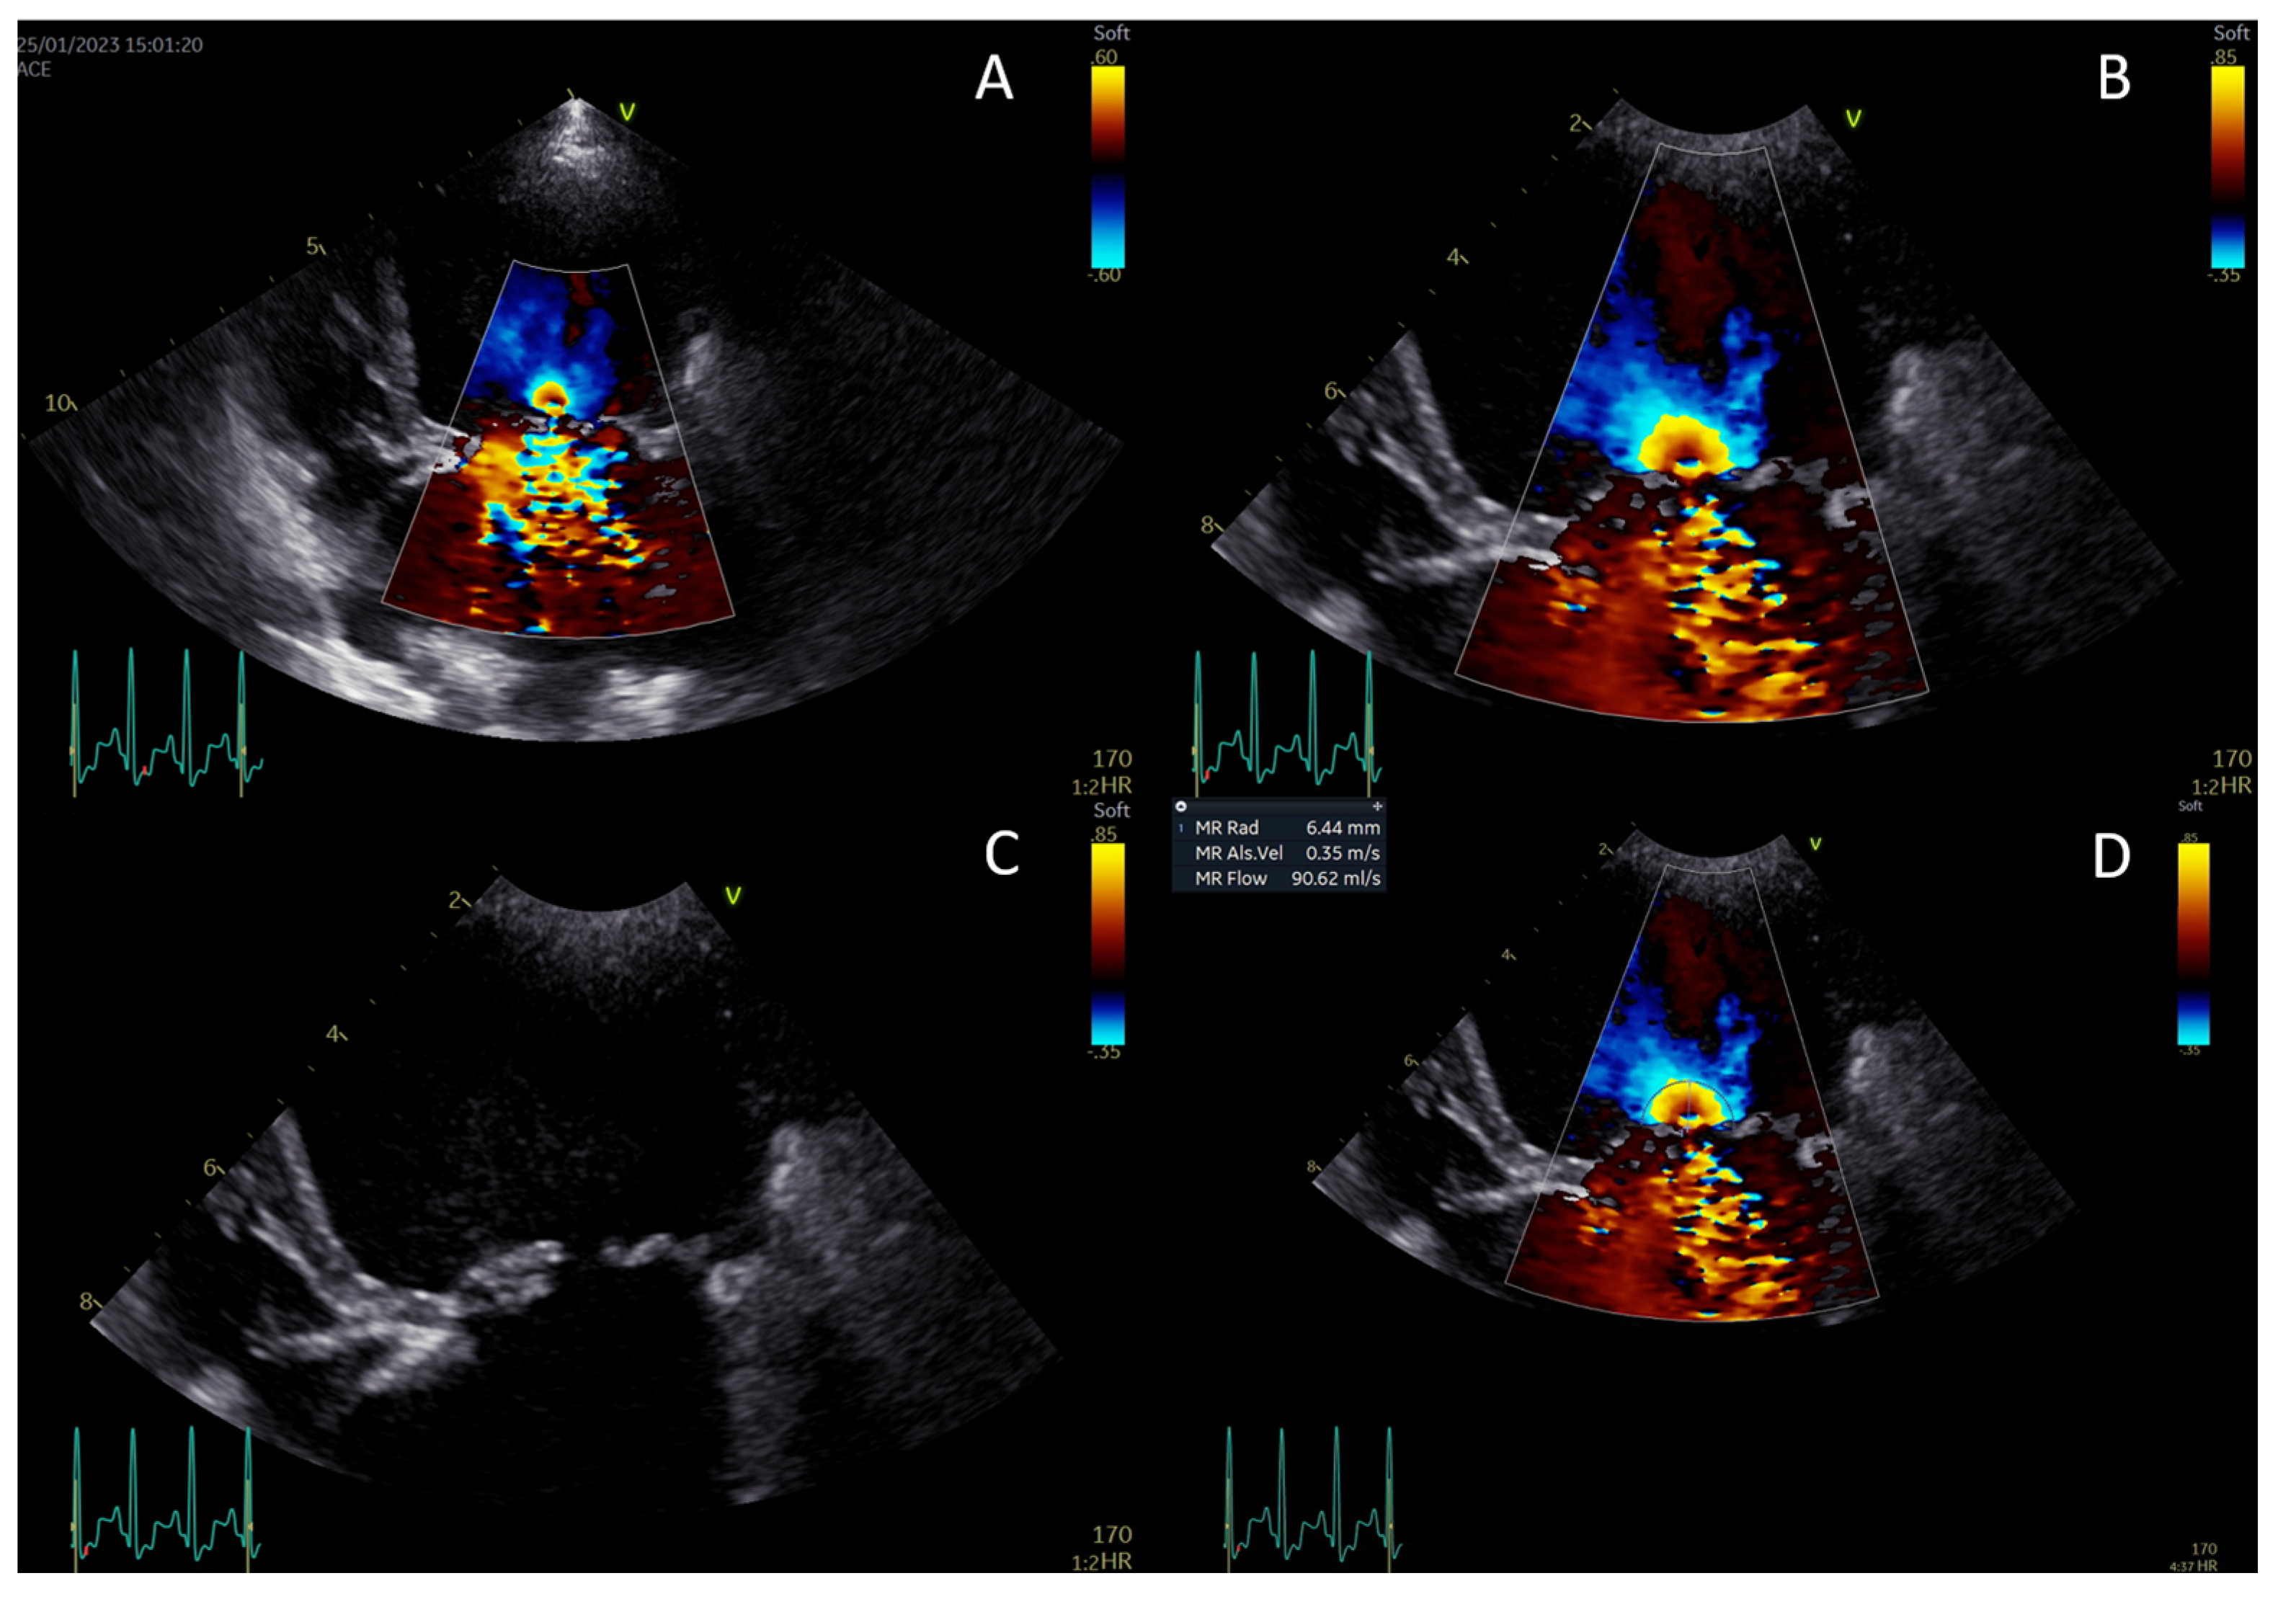

2.2. Echocardiography